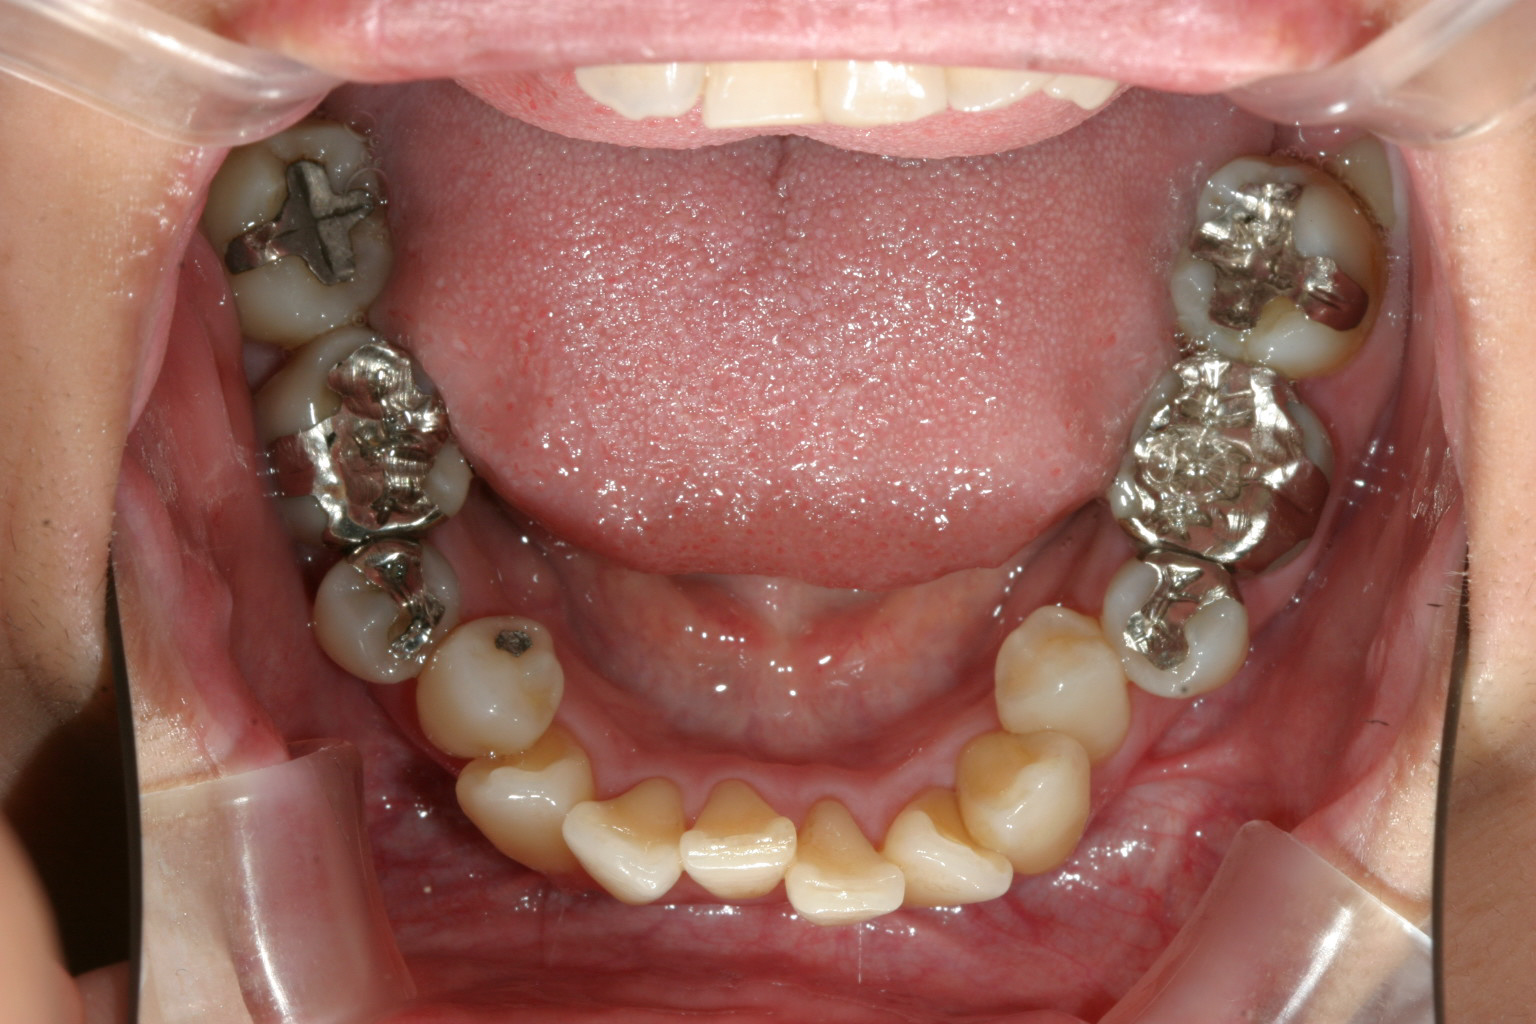

下顎も歯があちこち回転してますでしょ~ これはかなり大変です。

横からの見栄えも少し出てます。